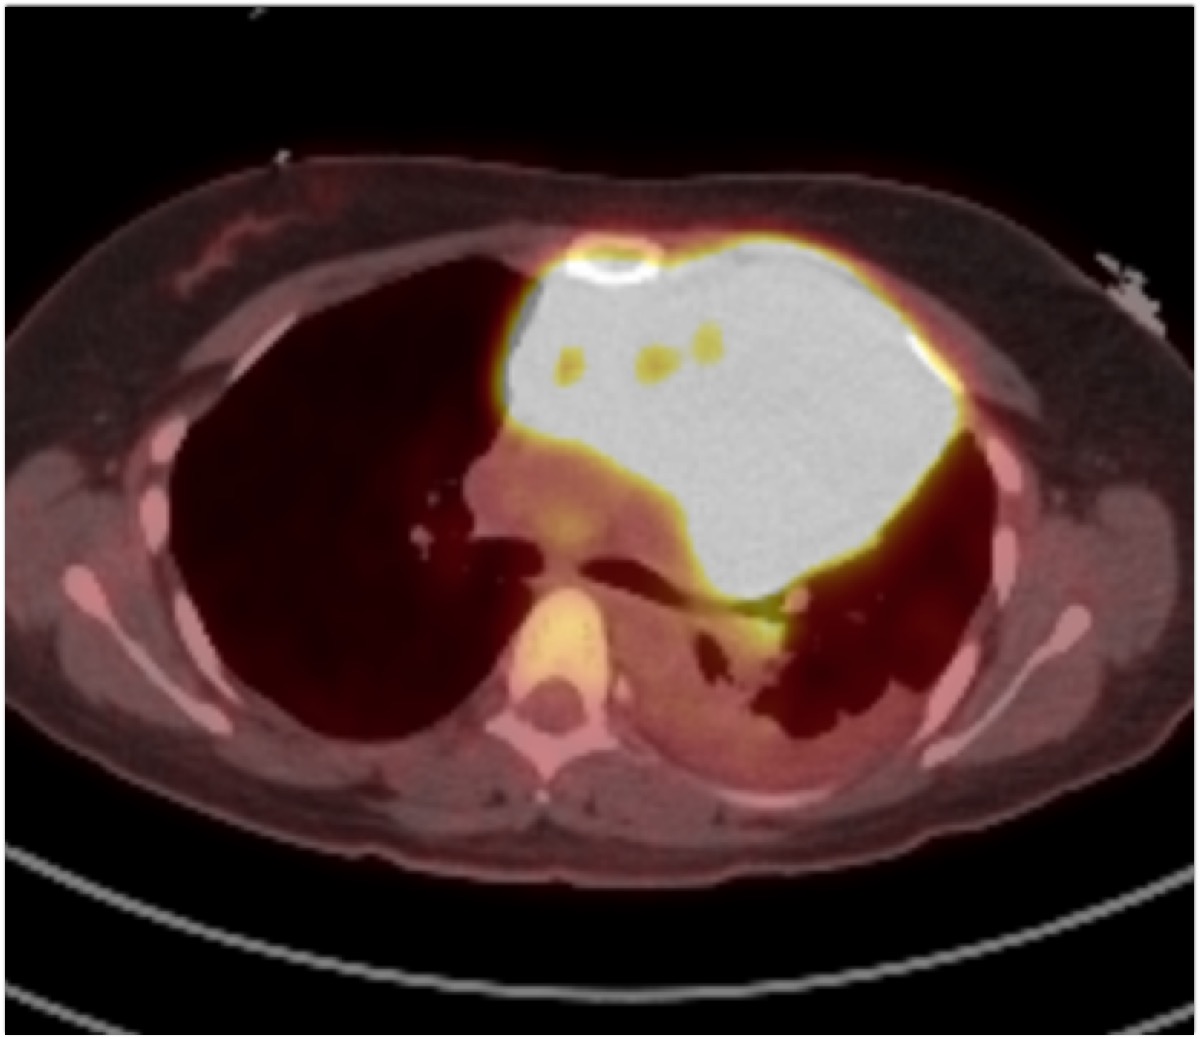

8) The most likely diagnosis in this case is?

clear cell renal cell carcinoma

large B-cell lymphoma

seminoma

renal abscess